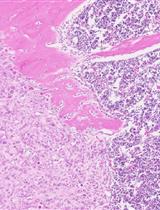

Gene rearrangements generate mixed-lineage leukemia (MLL) fusion genes, which cause highly aggressive acute leukemia. MLL-rearrangements are often associated with few additional genetic alterations and poor clinical outcomes (Andersson et al., 2015). Wild-type MLL enhances and maintains the expression of a subset of genes, including homeobox (Hox) genes, to stimulate the expansion of immature progenitors (Jude et al., 2007). The expression of Hoxa9 and Meis1 is highest in the immature progenitor/stem cell fraction, but gradually declines as cells differentiate, and eventually diminishes in terminally-differentiated cell fractions (Somervaille and Cleary, 2006; Yokoyama et al., 2013). The MLL fusion protein constitutively up-regulates the expression of target genes, including Hoxa9 and Meis1, to immortalize immature progenitor cells and cause leukemia in vivo (Ayton and Cleary, 2003; Lavau et al., 1997). To date, more than 130 different MLL-rearrangements have been identified (Meyer et al., 2017). Two-thirds of MLL-rearranged leukemia cases are caused by fusion with a gene that is part of the AF4 family-ENL family-P-TEFb (AEP) complex (Yokoyama et al., 2010). The MLL fusion proteins constitutively form an MLL/AEP hybrid complex on the target chromatin (Okuda et al., 2014; Yokoyama et al., 2010), which further associates with the SL1 complex to activate RNA polymerase II-dependent transcription (Okuda et al., 2015 and 2016). AEP-mediated transactivation of MLL target genes transformed myeloid progenitors ex vivo, but did not cause leukemia in vivo, which suggested that other function is additionally required for in vivo leukemogenesis (Okuda et al., 2017). Recently, we showed that the ability to recruit the DOT1L complex is necessary to cause leukemia in vivo in addition to the ability to recruit AEP using in vivo leukemogenesis model. Thus, the combinatorial use of the in vivo leukemogenesis model and myeloid progenitor transformation assay is necessary to dissect the functional properties of oncogenes. In this protocol, we describe the in vivo leukemogenesis model using retroviral transduction in detail.